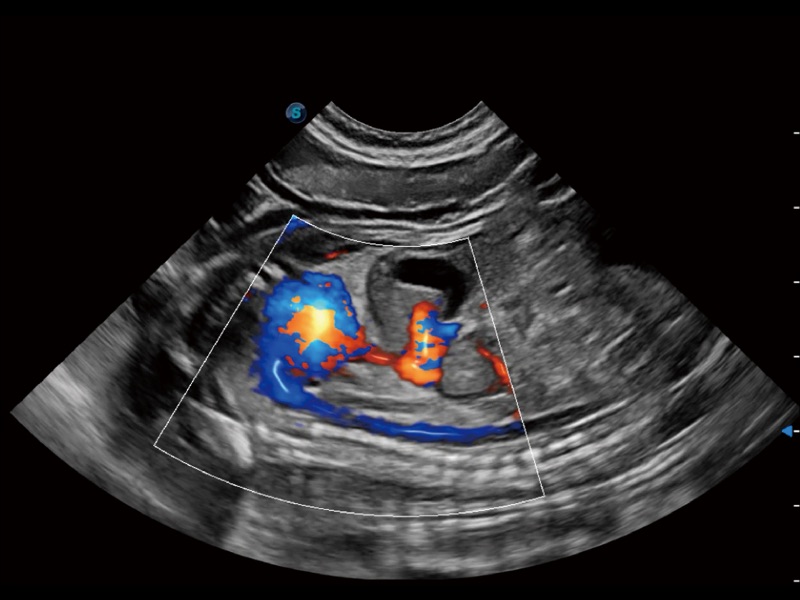

优异的基础图像

(犬)左室长轴血流